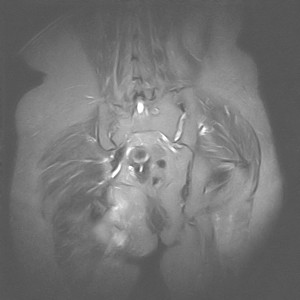

图像太差了 1、右侧臀肌旁脓肿? 建议增强 2、左侧股骨头坏死并半脱位

1、左侧股骨头坏死并髋关节半脱位;

2、右侧臀肌感染,(可能褥疮所致)